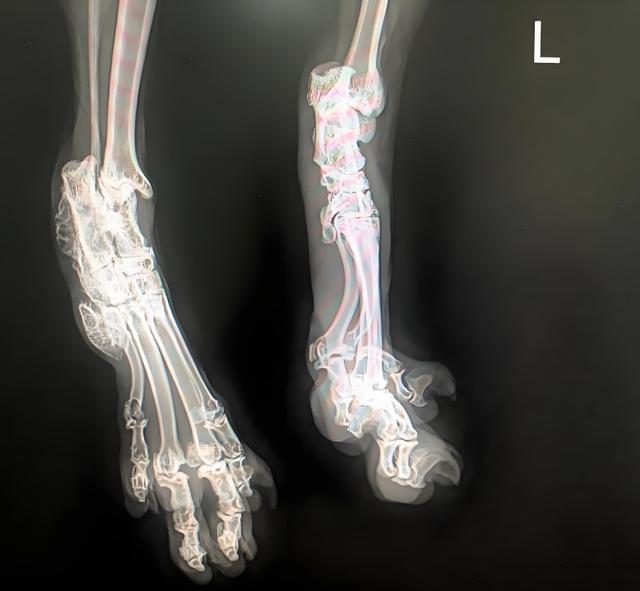

@濮阳丹妮宠物医院史大夫 折耳猫发病X光片

国际兽医协会(WSAVA)2023年报告证实:折耳猫因Fd基因突变,软骨病发病率高达92.3%。央视《焦点访谈》暗访山东某繁殖场,种猫因骨骼变形被铁链锁住配种,幼崽未满月已出现跛行。

《兽医内科学》研究显示:折耳猫的"萌耳"实为COL2A1基因缺陷标志,2月龄起全身软骨加速溶解,最终导致:

脊柱骨刺密度超健康猫370%(牛津大学2022年CT扫描数据)67%的折耳猫因胸骨畸形窒息死亡(北京农学院解剖统计)